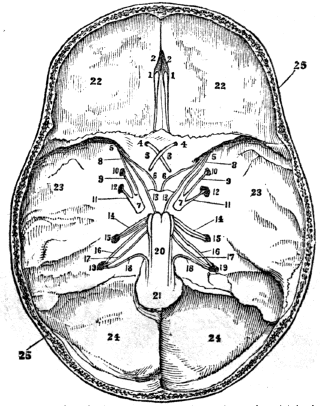

| 36. | Anatomy of the Nervous System, | 327 |

| 37. | Anatomy of the Nervous System, continued, | 340 |

| 38. | Physiology of the Nervous System, | 346 |

| 39. | Hygiene of the Nervous System, | 358 |

| 40. | Hygiene of the Nervous System, continued, | 368 |

| 41. | The Sense of Touch, | 378 |

| 42. | Anatomy of the Organs of Taste, | 384 |

| 42. | Physiology of the Organs of Taste, | 386 |

| 43. | Anatomy of the Organs of Smell, | 389 |

| 43. | Physiology of the Organs of Smell, | 391 |

| 44. | Anatomy of the Organs of Vision, | 394 |

| 45. | Physiology of the Organs of Vision, | 404 |